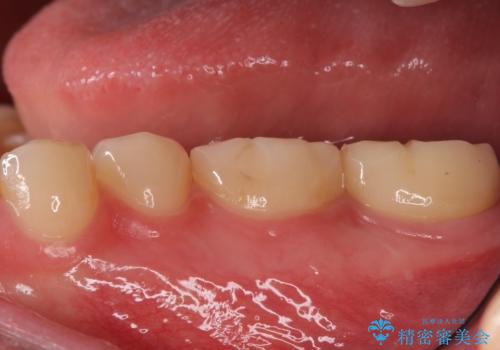

奥歯がしみる 神経を温存する治療

- 奥歯がしみるとのことで来院されました。

検査の結果、古い詰め物の裏側に虫歯ができていること(二次う蝕)が確認されたため、治療していくこととなりました。

- 左下7 生活歯髄療法:33,000円 仮歯+ジルコニアクラウン:11,000円+121,000円費用は治療当時の料金となります

虫歯が大きくても、今回のように神経を温存することができる場合があります。